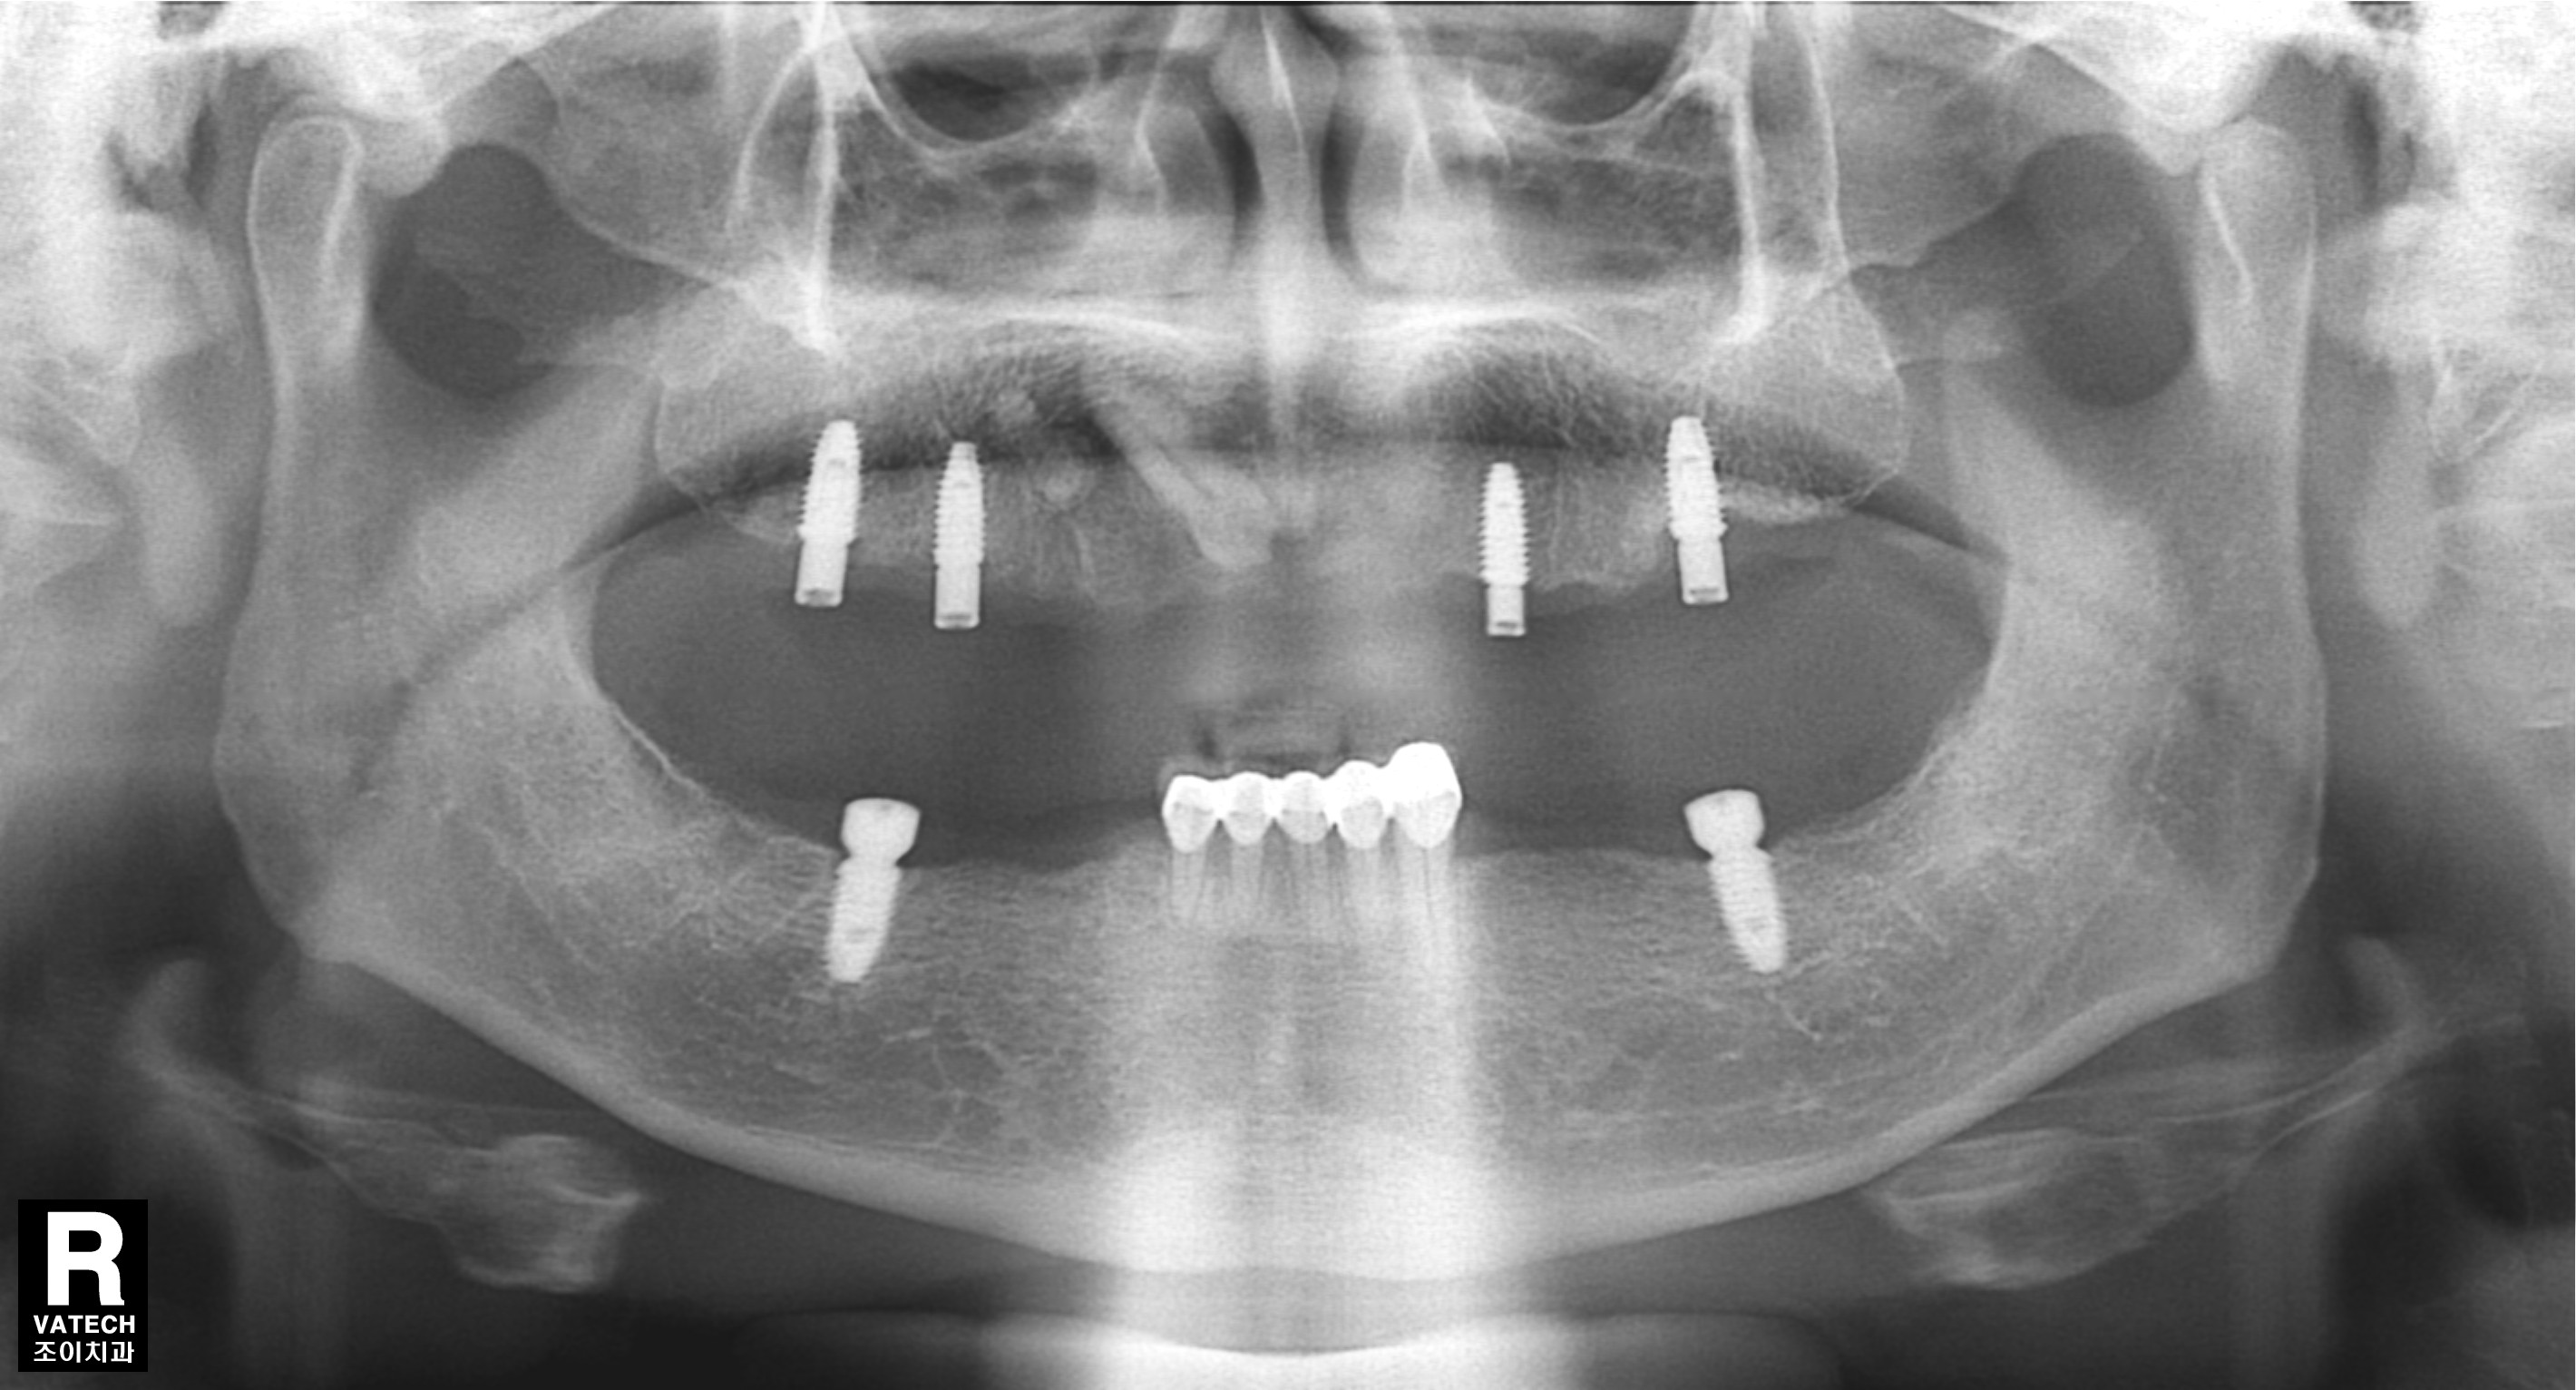

[임플란트] 제목 : 임플란트 지지 틀니

소수의 임플란트로 틀니사용을 편하게. .